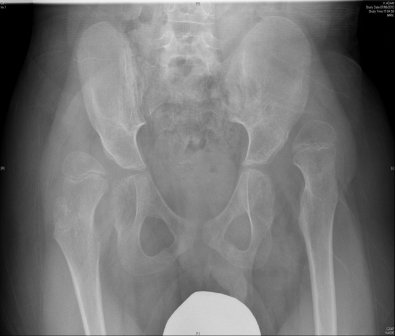

Αυτό το παιδί υποβλήθηκε σε αμφοτερόπλευρη χειρουργική στα ισχία και χαλάρωση μαλακών μορίων από τον Δρ Ζένιο σε μια μόνο επέμβαση